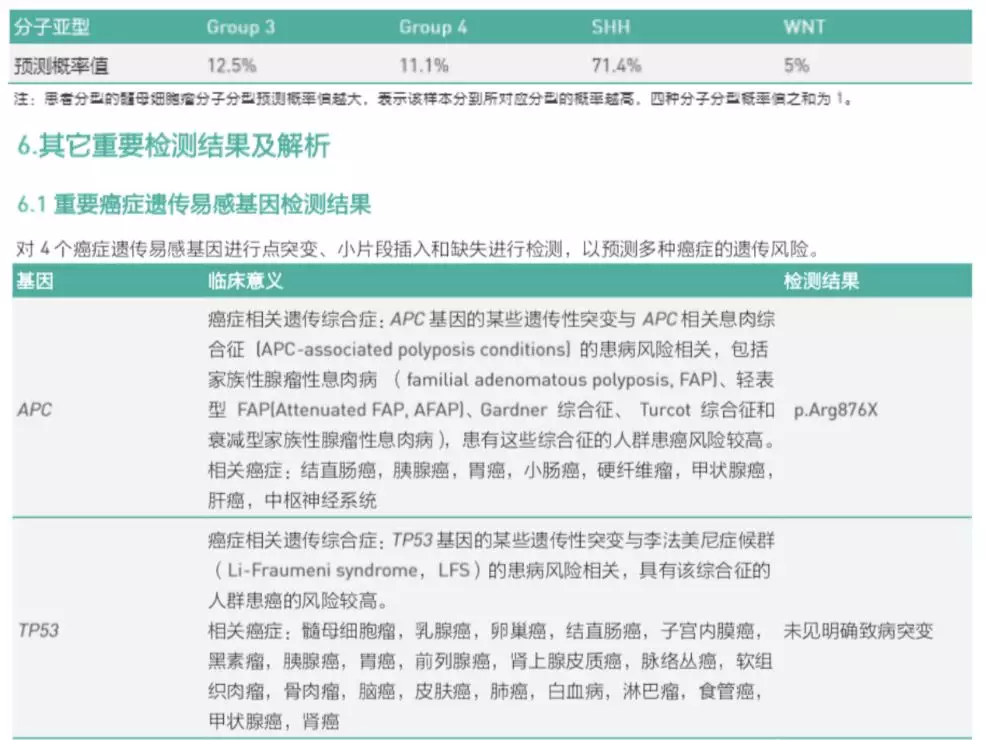

2017年11月10日,患者术后病情平稳,恢复良好,为了根据分子分型选择后续治疗方案,采取基因检测进行诊断(泛生子髓母分子分型检测39panel)。

结合WHO中枢神经系统肿瘤分类指南(2016),基因检测结果显示:患者属于髓母细胞瘤, SHH激活及TP53野生型(图3、图4、图5)。分子评估其危险等级倾向于标危,需结合临床共同判断文献报道预后的5年中位总生存率为76%,但有APC遗传可能有其他肿瘤发生的风险。

图3. Panel 39基因检测结果

图4. Panel 39基因检测结果